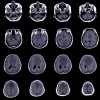

Lesi serebral dengan penyangatan cincin merupakan salah satu temuan tersering pada pindaian otak. Lesi tersebut memiliki beragam diagnosis banding yang merupakan tantangan tersendiri dalam menentukan diagnosis dan tata laksana yang tepat. Lesi serebral dengan penyangatan cincin dapat disebabkan oleh neoplasma, inflamasi, infeksi, penyakit autoimun, hingga penyebab vaskular. Pencitraan radiologi, keterangan klinis yang lengkap, dan status imunologi pasien dapat membantu mengarahkan ke etiologi dan tata laksana yang sesuai.[1]

Etiologi dari lesi serebral dengan penyangatan cincin sangat beragam dan memiliki pola bentuk yang beragam. Etiologi dapat berupa proses infeksi, neoplasma, inflamasi, ataupun vaskular.

Neoplasma baik primer ataupun sekunder yang dapat menampilkan lesi dengan penyangatan cincin adalah glioblastoma, glioma derajat rendah, limfoma, dan metastasis serebral. Penyebab infeksius meliputi tuberkuloma, neurosistiserkosis, abses otak piogenik, toxoplasmosis, infeksi jamur, dan neurosifilis. Proses inflamasi non infeksius dapat meliputi kelainan demielinasi, sarkoidosis, penyakit Behcet, dan ensefalopati pasca radiasi. Penyebab vaskular dapat meliputi trombosis vena serebral dan kelainan vaskulitis lainnya.[1]

Schwartz et al dalam penelitiannya menemukan bahwa sekitar 40% lesi serebral dengan penyangatan cincin memiliki etiologi glioma, 30% metastasis otak, 8% abses, dan 6% merupakan kelainan demielinasi. Sisa 16% lainnya disebabkan etiologi lain seperti infark, limfoma, dan nekrosis radiasi. [3]